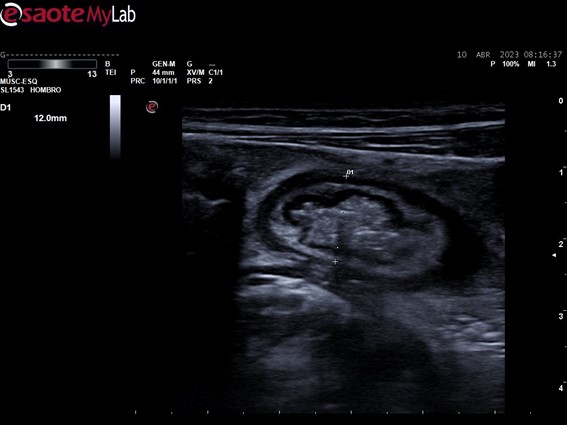

Hombre de 44 años con dolor abdominal difuso, vómitos y diarrea, con episodios previos recurrentes de años de evolución: enfermedad de Crohn con múltiples estenosis en íleon.